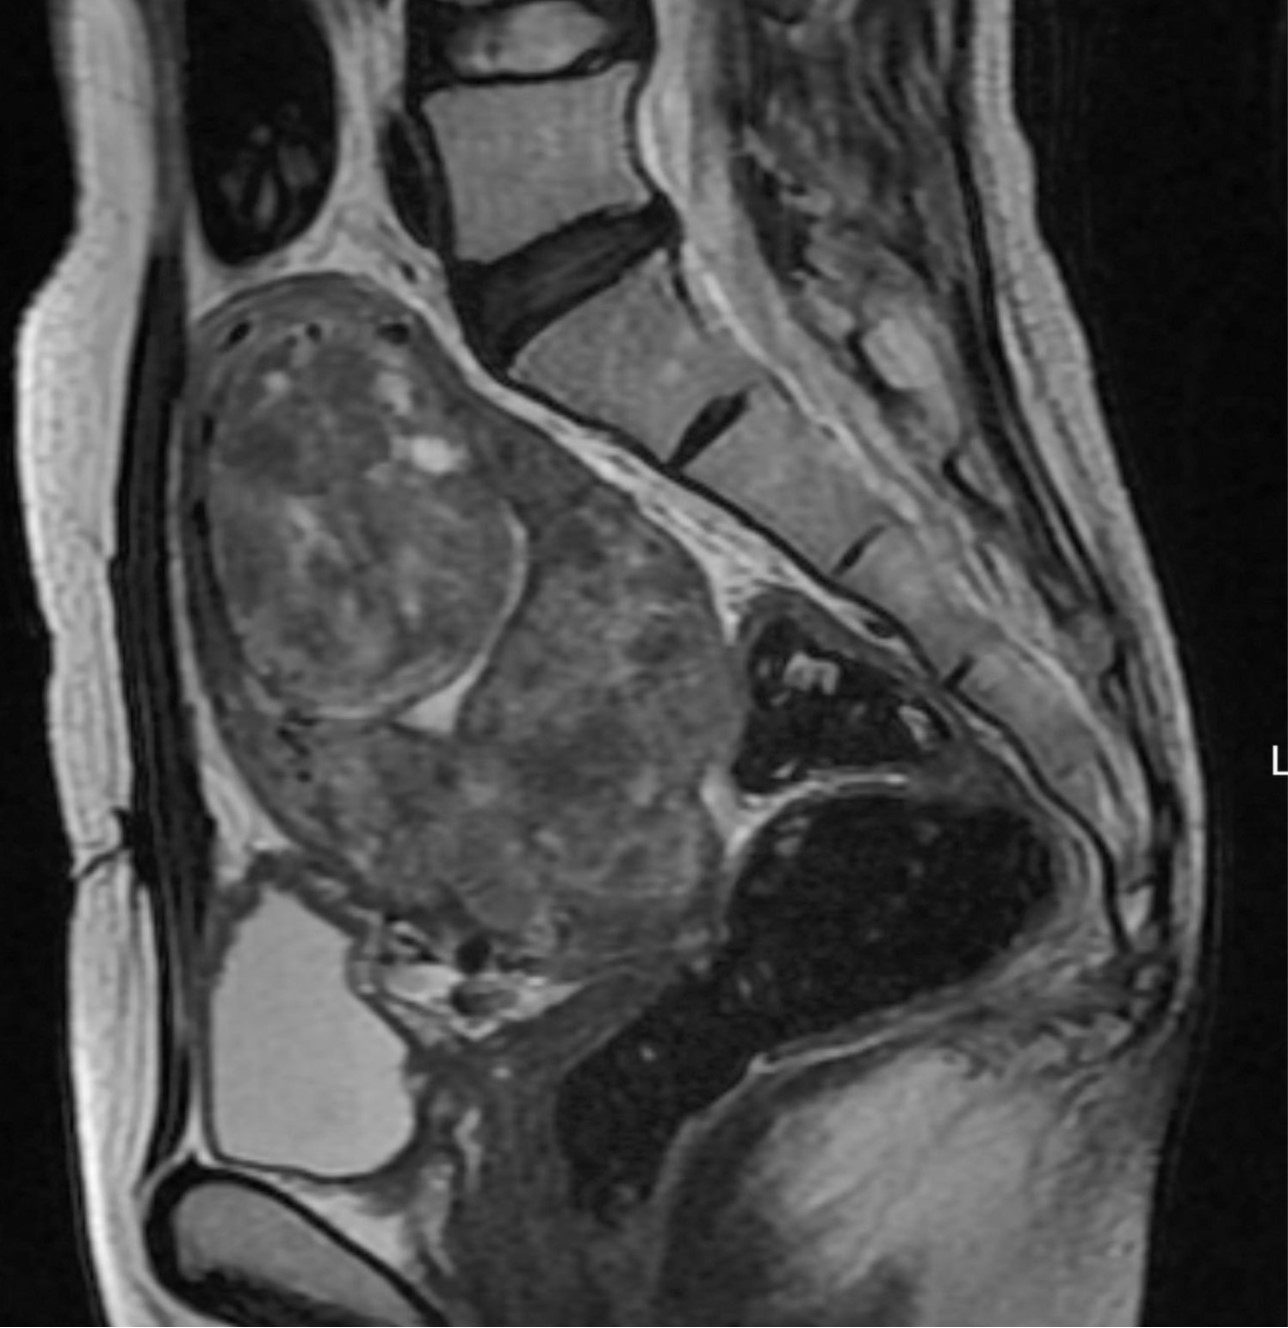

Fig. 3.

Fig. 3. T2-weighted sagittal MR image obtained 3 months after uterine artery embolization shows necrotic changes in most uterine myomas. The largest one shows 84.4% volume reduction.

초음파 유도 하에 우측 대퇴동맥을 천자하여 5F sheath(Terumo, Tokyo, Japan)를 삽입하였다. Pigtail 카테타(Cook, Bloomington, USA)를 복부 대동맥에 위치시킨 후 골반동맥조영술을 시행한 결과, 좌측 자궁동맥은 커져 있었으나, 우측 자궁동맥은 위축되어 있었다(Fig. 2A). 동시에 우측 바깥엉덩동맥으로부터 기시하는 비대해진 우측 변이 난소측부동맥이 보였다(Fig. 2A). 5F RUC 카테타(Cook, Bloomington, USA)를 우측 외장골동맥에 진입시키고 Microferret 카테타(Cook, Bloomington, USA)로 우측 변이 난소측부동맥을 선택하였다. 난소동맥조영술상에서 우측자궁동맥은 변이 난소측부동맥에 의하여 완전히 대치되어 있었다(Fig. 2C). 양측 자궁동맥 색전술을 시행한 뒤, 추가로 355-500um 크기의 polyvinyl alcohol 색전입자(Contour, Boston Scientific, Natick, USA)를 사용하여 우측 변이 난소측부동맥 색전술을 시행하였고, 10번의 심장박동 동안 동맥 내에 조영제의 정체가 보일 때까지 색전술을 시행하였다. 색전술 후 3개월째 시행한 자기공명영상에서 대부분의 자궁근종들은 완전히 괴사되었으며, 가장 큰 것은 84.4%의 부피감소를 보였다(Fig. 3). 시술 전 증상을 10점으로 가정 하였을 때, 색전술 후 1년째 되는 시점에 생리과다의 증상 점수는 4점으로 감소하였다.